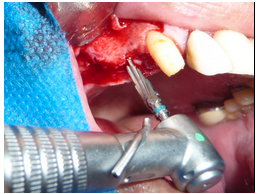

A técnica de incisão de descolamento de retalho para a utilização do aparelho piezoelétrico não difere da técnica convencional ditada do Tatum (figura 3).

Para o acesso à cavidade sinusal se faz uso de ponta piezocirúrgica esférica, diamantada (figura 4). O aparelho utilizado foi um Piezosonic Driller ®. A demora na osteomia na osteotomia é compensada pela precisão e na proteção à membrana sinusal.